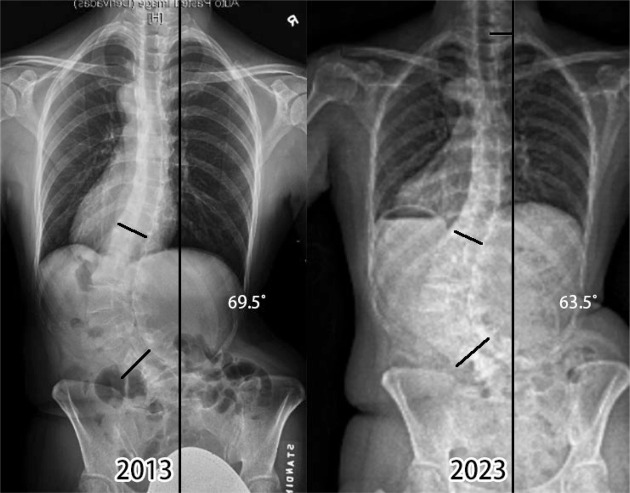

【目的】本研究探讨绝经后胸腰椎弯曲妇女进行脊柱侧凸特异性锻炼是否与脊柱弯曲稳定有关。【病例描述】我们描述了三名绝经后胸腰椎侧凸的妇女进行了大约十年的脊柱侧凸专项锻炼的结果。病例1骨密度正常,胸腰椎侧凸超过64°,每天在家坚持锻炼半小时。病例2和病例3骨质减少,胸腰椎弯曲度分别为64°和45°。他们在八年的时间里很少做这些练习,特别是在新冠肺炎爆发的三年里,他们停止了这些练习。[结果]三个案例的结果不同。病例1效果最好,胸腰椎弯曲稳定,无疼痛。病例2和病例3有弯曲性进展,疼痛轻微,需要偶尔使用止痛药。【讨论】我们的研究结果表明,定期的脊柱侧凸专项锻炼、良好的骨矿物质密度和脊柱侧凸稳定之间存在潜在的关系。需要更多的研究来进一步了解运动、骨骼健康和脊柱侧凸进展之间的相互作用。

[Purpose] The study investigates whether performing scoliosis-specific exercises is related to curve stabilization in postmenopausal women with a thoracolumbar curve. [Case Description] We describe the outcome of three postmenopausal women with thoracolumbar scoliosis performing scoliosis-specific exercises for around ten years. Case 1 had a normal bone mineral density and thoracolumbar scoliosis over 64° and consistently performed the exercises at home for half an hour daily. Cases 2 and 3 had osteopenia and thoracolumbar curves of 64° and 45°, respectively. They did the exercises sparingly over eight years, particularly during the three years of COVID-19, when they stopped doing the exercises. [Outcome] The outcomes of the three cases differ. Case 1 had the best result, with the thoracolumbar curve stabilized and no pain. Cases 2 and 3 had curve progression and had mild pain, requiring occasional pain medication. [Discussion] Our findings suggest a potential relationship between regular scoliosis-specific exercises, good bone mineral density, and scoliosis stabilization. More research is needed to further our understanding of the interplay between exercise, bone health, and scoliosis progression.